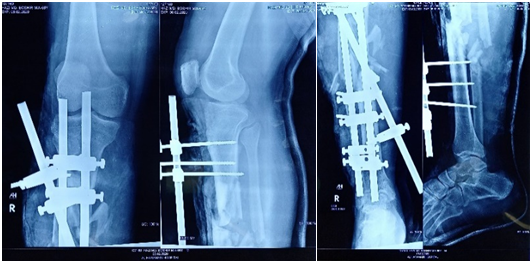

Under general anaesthesia with two units of whole blood in hand, the wound was opened. Through debridement and surgical toileting were done. On per-operative examination there were hugely comminuted de-touched periostiual bone fragment with extensive soft tissue loss. Radiologically it was a severely comminuted fracture with one small fragment of bone loss and displacement (Figure 1).

Bone was stabilized by uniaxial External Fixator (Ex-Fix) (Figure 2). Keeping in mind that 2nd look debridement and flap coverage has to be done later. The distal vascularity was checked after fixation (temporary Ex-Fix). The dorsalis pedis and posterior tibial vessel were intact. Neurological status was almost normal except some sensory loss over the proximal part of dorsum of foot. Postoperative recovery was uneventful and dressing was changed when it was socked. On 2nd post-operative day (POD) the wound was exposed under epidural anasesthesia and the secondary debridement was done keeping the neurovascular tissue with coverage by flash of muscle till partially viable.